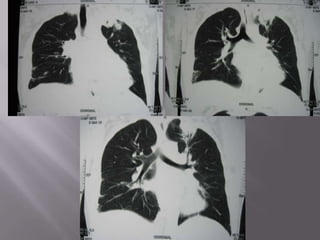

   Consolidation with air bronchogram in the

apicoposterior segment of left upperlobe

   Minimal right pleural effusion with basal

atelectasis

   Moderate pericardial effusion